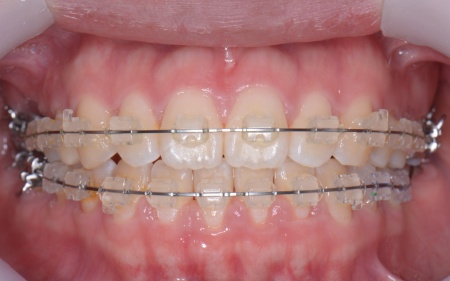

その後、全体の噛み合わせを改善するため、矯正治療を開始しています。

矯正治療では、歯に小さなボタンのような装置を取り付け、そこにワイヤーを通して歯を動かすマルチブラケット装置を使用しています。

矯正がある程度進んだ段階で、右上と左下のインプラント手術を実施しました。

インプラント手術後は矯正治療の仕上げを行い、装置を外しています。